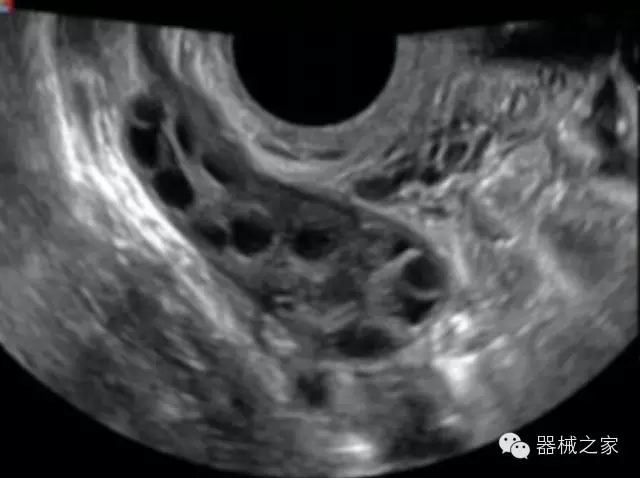

經(jīng)典產(chǎn)品:S8EXP

臨床圖片賞析

全面的術(shù)中探頭解決方案

·小凸探頭:開放性手術(shù),實(shí)時(shí)監(jiān)測(cè)病灶位置,提高手術(shù)成功率,可應(yīng)用于麻醉科、肝膽外科、腫瘤外科、神經(jīng)外科、泌尿外科等手術(shù);

·L型線陣探頭:高分辨率圖像,清晰顯示病灶位置,提高手術(shù)成功率,可應(yīng)用于麻醉科、胸外科、肝膽外科、腫瘤外科、神經(jīng)外科、泌尿外科等應(yīng)用;

·MPTEE:經(jīng)食道探頭術(shù)中監(jiān)測(cè),可測(cè)量心臟前負(fù)荷(左室舒張末期大小、右房大?。⑿呐叛?、后負(fù)荷、收縮功能、室壁運(yùn)動(dòng)分析、肝靜脈血流(與中心靜脈壓相關(guān))等,術(shù)后還能及時(shí)評(píng)估手術(shù)效果評(píng)估;

·獨(dú)有的大角度及實(shí)時(shí)溫控技術(shù),能同一切面顯示宮頸及宮體,有效減低了患者的痛苦,及保護(hù)粘膜保證了醫(yī)療安全;